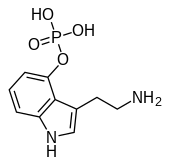

| Norbaeocystin | Fungi | 4-OPO3H2 | H | H | 4-phosphoryloxy-tryptamine | 21420-59-7 |